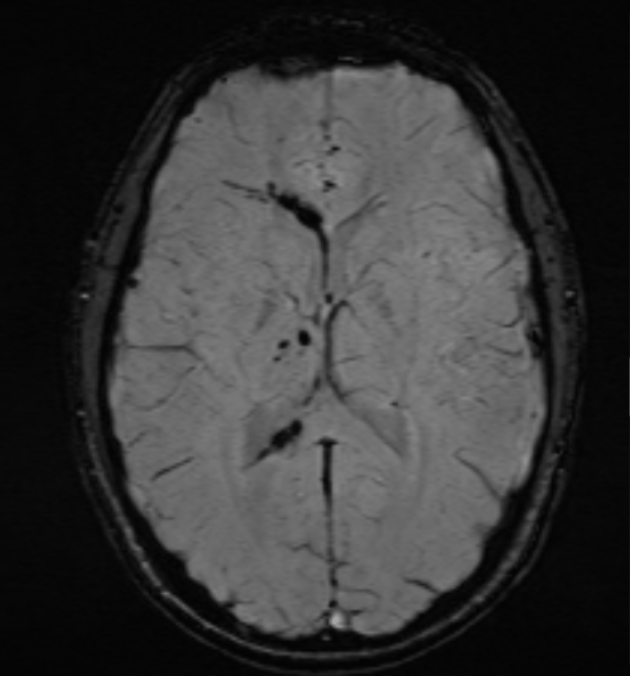

This environmental toxin can cause headache, nausea, vomiting, confusion, focal neurological findings, and the following appearance on neuroimaging.

What is carbon monoxide?